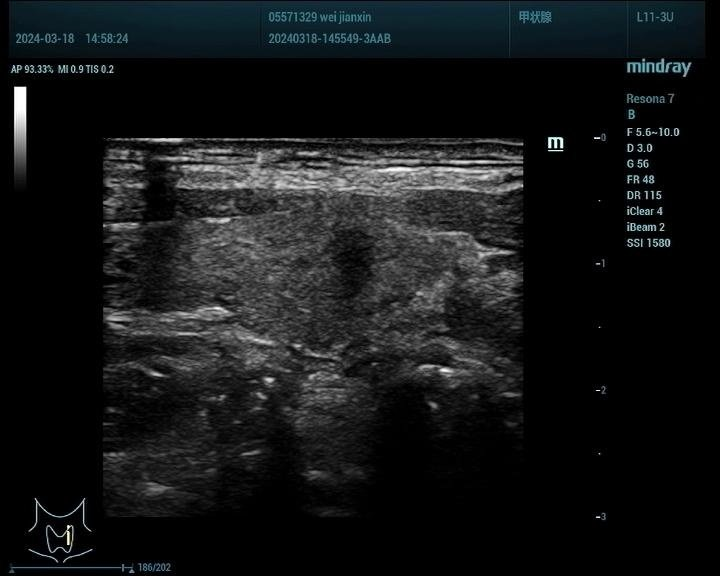

1、甲状腺:

观察甲状腺结节的血供情况:超声造影能够显示甲状腺结节的血供情况,有助于判断结节的活性及是否存在恶变倾向。

鉴别甲状腺结节的良恶性:通过超声造影,可以观察到结节的边界、形态、内部回声等特征,从而对结节的良恶性进行初步鉴别。

甲状腺癌病例